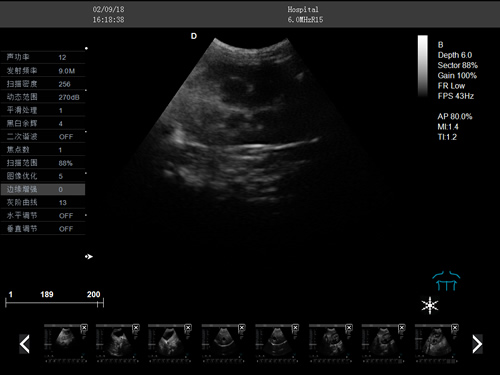

動物寵物超聲診斷儀

彩色多普勒動物超聲診斷儀

·中小動物的肝、膽,脾、腎、膀胱、子宮、妊娠等各組織器官的檢查和病變的診斷